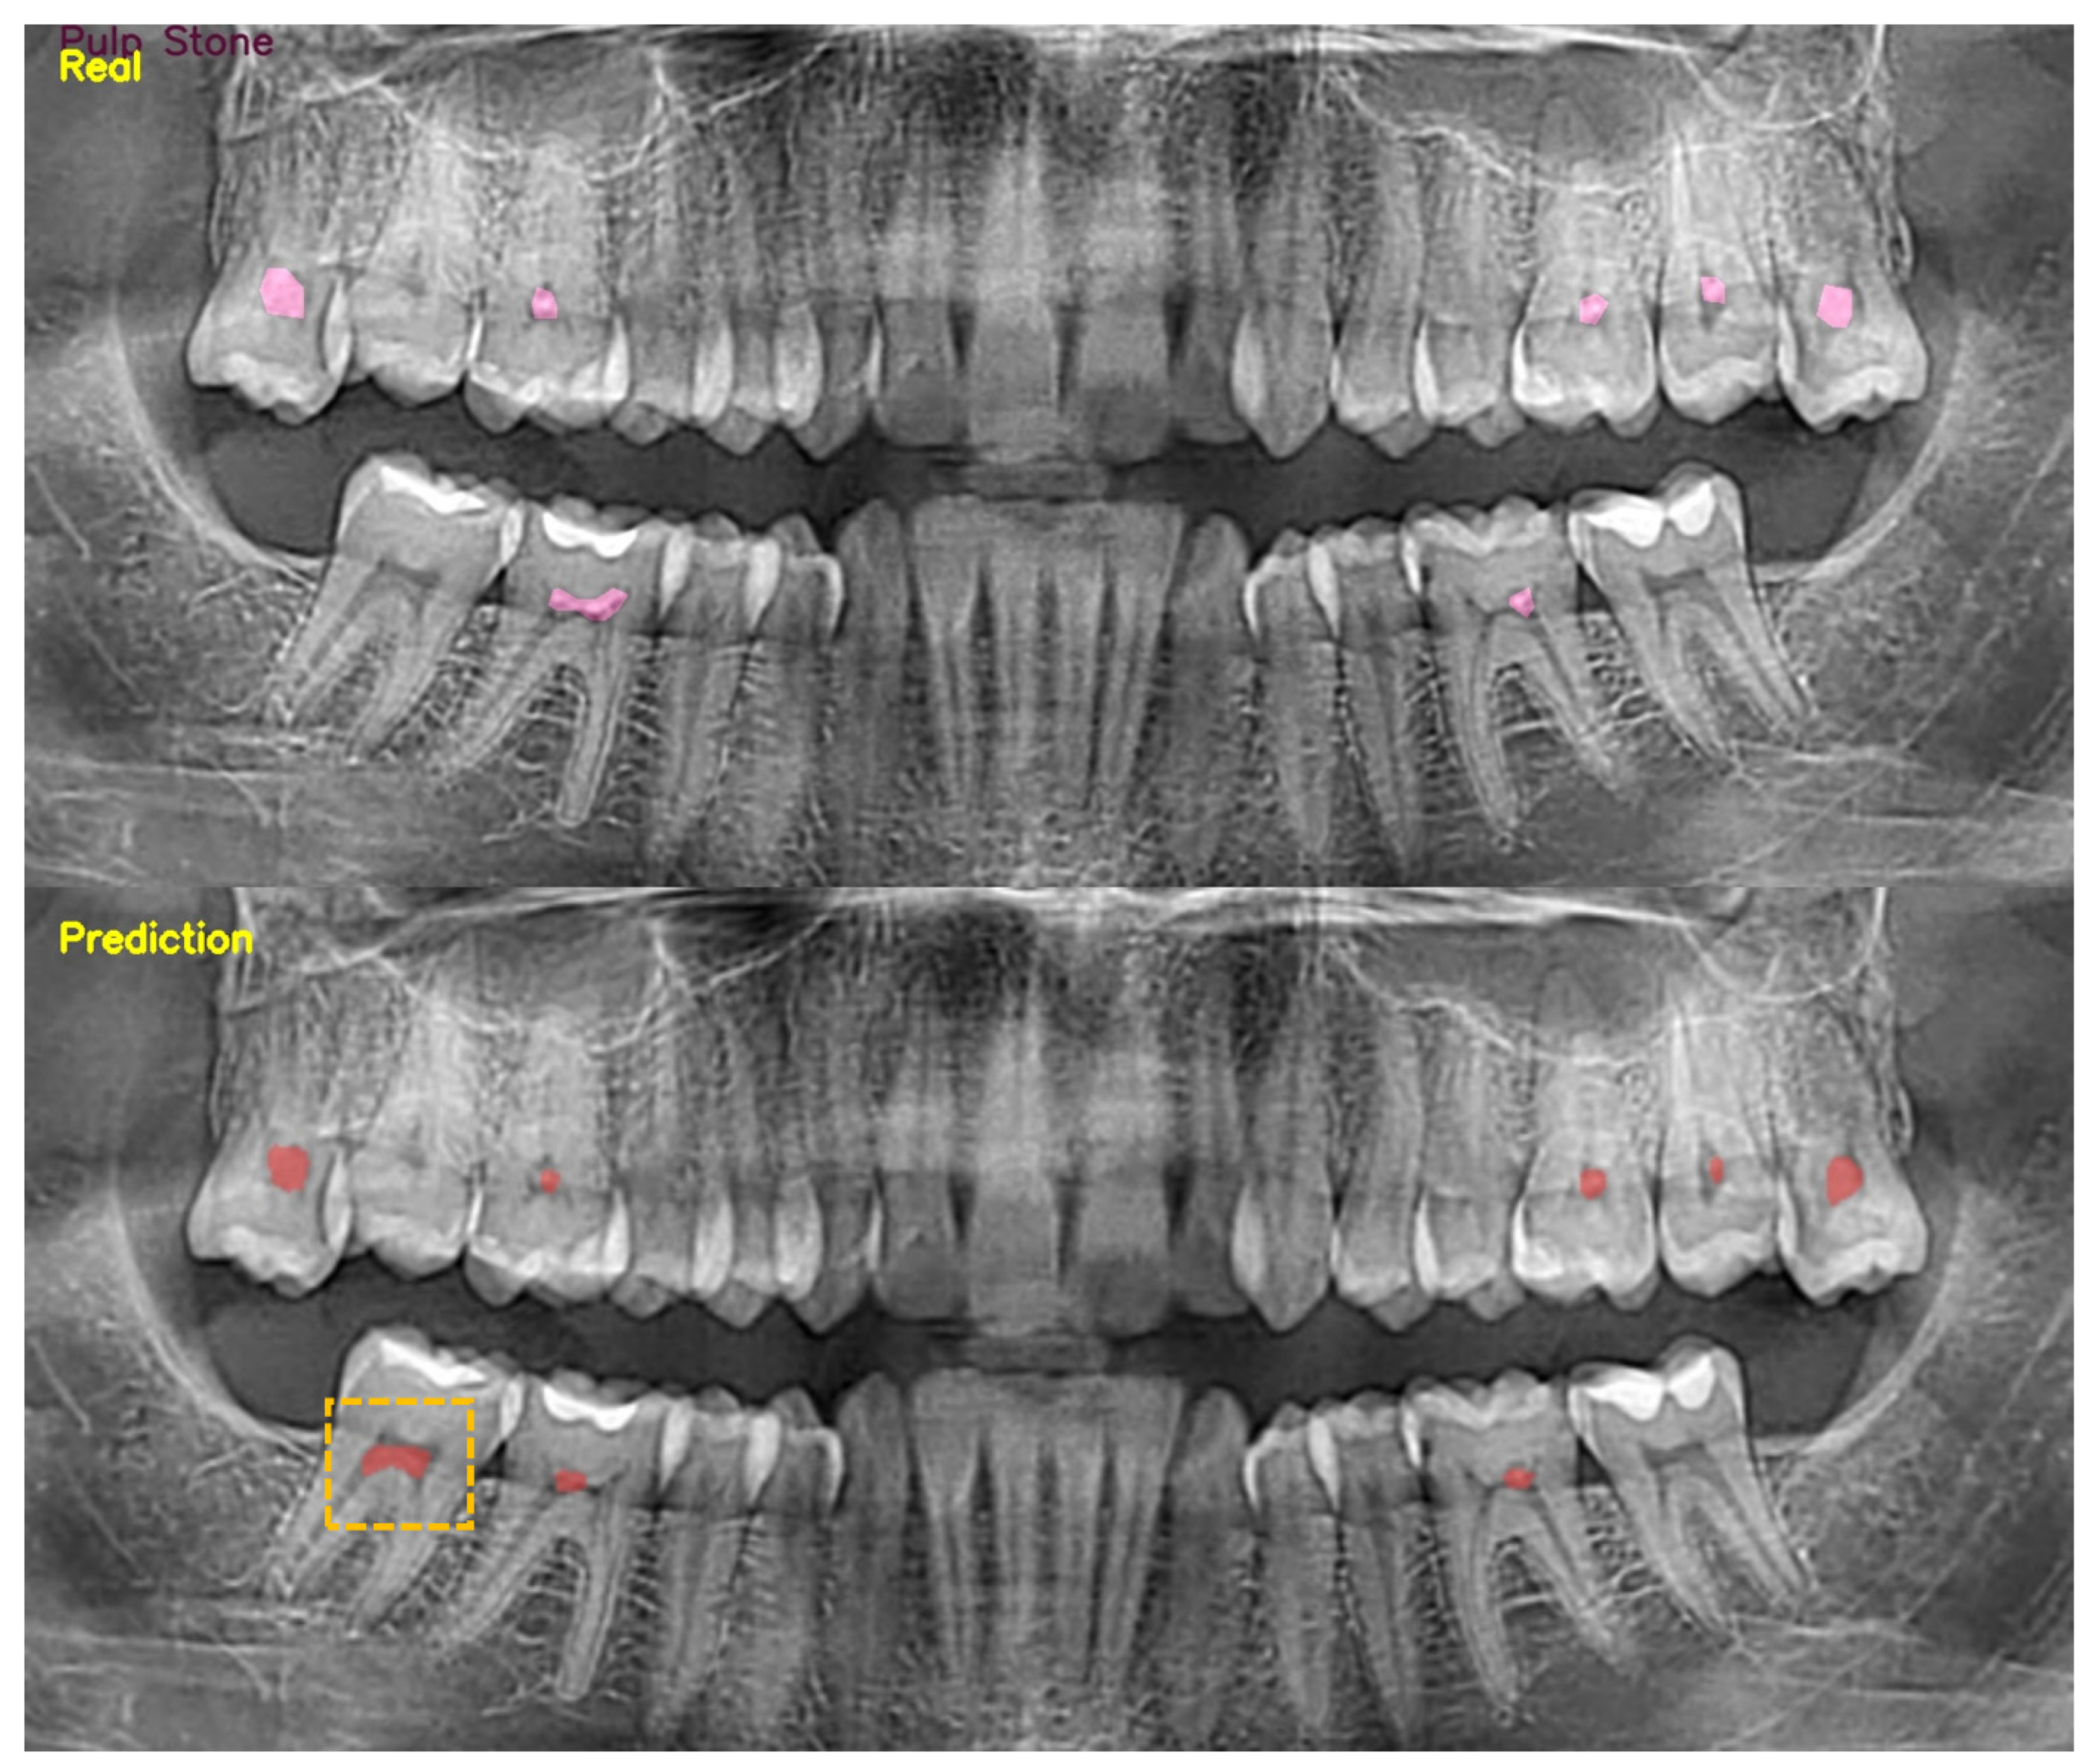

The Detection of Pulp Stones with Automatic Deep Learning in Panoramic Radiographies: An AI Pilot Study †

2. Material and Methods

3. Results